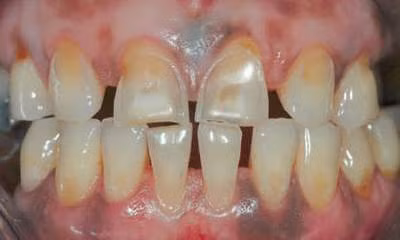

![]() |

| Răng bị mòn sinh lý. |

Mòn răng sinh lý còn gọi mòn răng-răng là sự mất tổ chức cứng do sự trượt lên nhau giữa các răng đối đầu dưới tác động của các tác nhân nội tại có thể là sinh lý hoặc bệnh lý. Khi bị mòn răng sinh lý thường có thứ tự mòn răng tương đối ổn định: mòn rìa cắn trước, sau đó mòn đến các núm ngoài răng dưới và núm trong răng trên. Mặt tổn thương có thể phẳng trong giai đoạn mòn men, khi ngà răng bị bộc lộ thường bắt màu nâu, tốc độ mòn của ngà nhanh hơn tốc độ mòn men nên tổn thương có dạng hình lõm đáy chén. Các tổn thương của hai răng đối đầu thường khớp khít vào nhau. Vị trí và mức độ tổn thương phụ thuộc vào đặc điểm khớp cắn: các điểm chạm sớm và các điểm cản trở cắn là các điểm mòn răng sinh lý thường xuất hiện sớm. Khi mòn nhiều gây nhạy cảm răng, tủy phản ứng tạo ngà thứ phát để bảo vệ tủy.